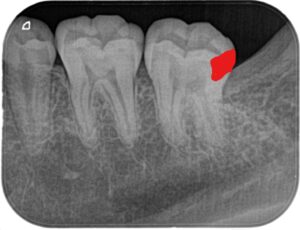

親知らずを抜いた後に小さいX線写真を撮ると第二大臼歯遠心に大きな虫歯がはっきりと写ってきました(下の赤い部分が虫歯です)

一般的には第二大臼歯の咬合面から大きく削り、インレーと呼ばれる詰め物を作ると思います。下の写真のオレンジ色の部分を削るため、虫歯の部分1に対して健康な部分を2~3ぐらい削ります。